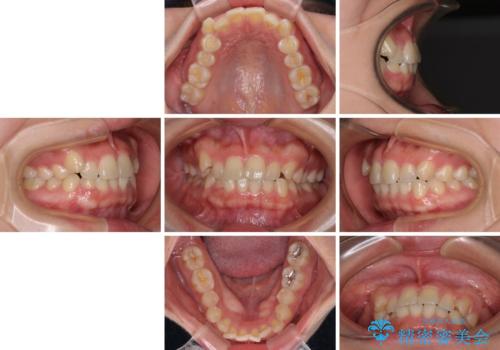

- 左右の八重歯を気にして来院された患者様です。

ワイヤー装置でもマウスピースでも対応可能な歯列でしたが、マウスピース矯正は自己管理が煩わしいとのことでワイヤー矯正を選択されました。

八重歯である犬歯は歯根が長いため、上顎前歯が出っ歯になるリスクがあるため、必要に応じてアンカースクリューを用いて奥歯を後方に移動させる可能性をお伝えしました。

舌の突出癖により上下前歯が開咬となりましたが、舌のトレーニングと顎間ゴムの使用により、元々の被蓋関係に改善することができました。

アンカースクリューを用いて、出っ歯仕上がりを回避し、正中位置も改善することができました。